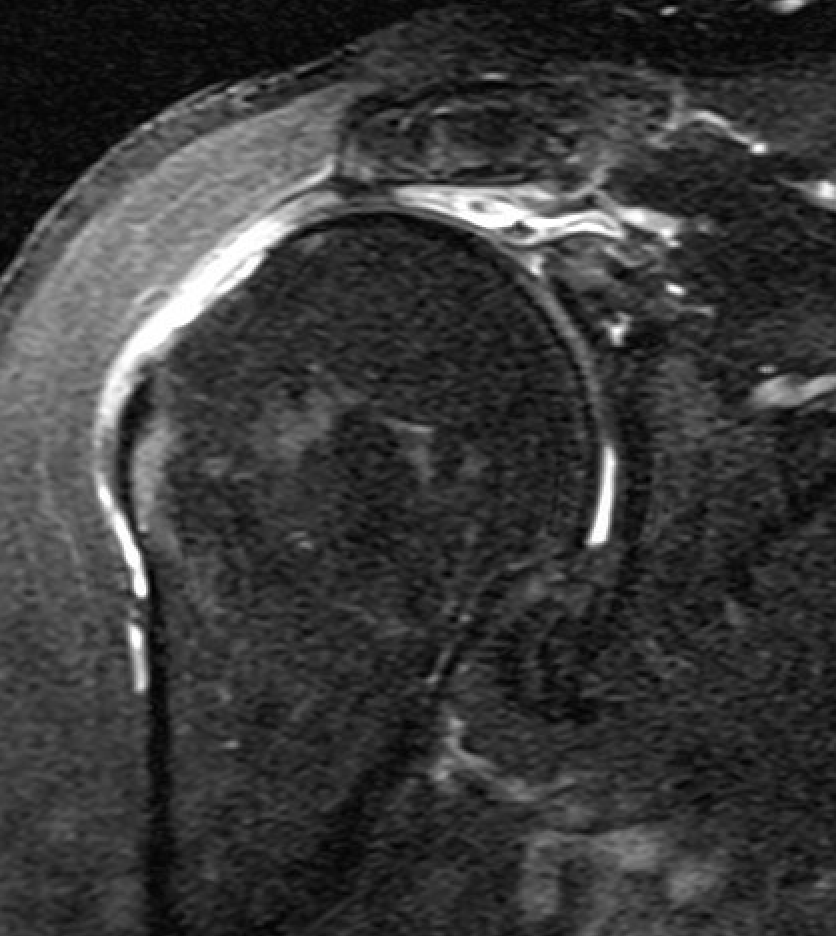

Full thickness rotator cuff tears

Partial bursal sided tear Partial articular sided tears

Small full thickness rotator cuff tear of supraspinatus - retracted to footprint

Large full thickness tear of supraspinatus and infraspinatus tendon - retracted to midhumeral head

Massive rotator cuff tear of the supraspinatus and infraspinatus tendon - retracted to glenoid